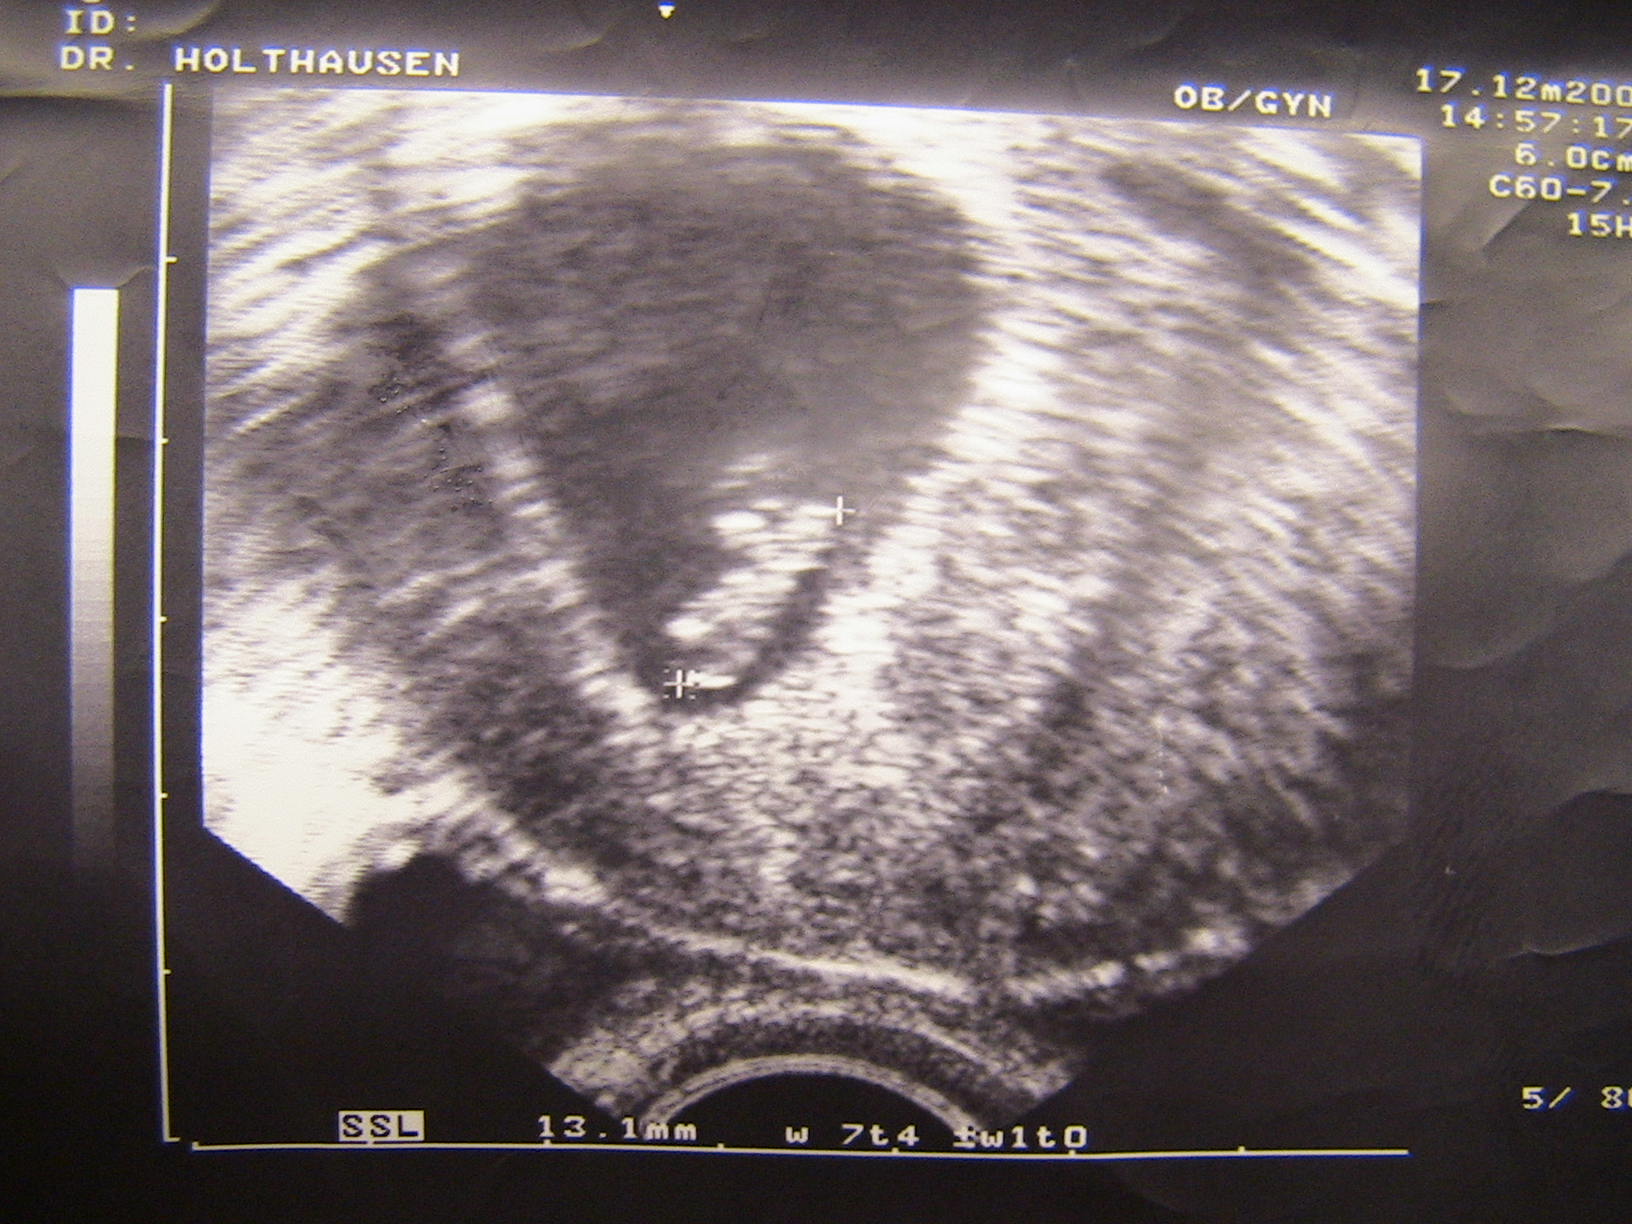

Wie Lily,und puhsig,,euch ja schon berichtet hatte bin ich mir Blutungen ins Kh ich hatte mega grosse Angst meine Beine zitterten so das der doc schon sagte halten sie mal die beine ruhig aber es ging nicht ,auf dem US war dann die Fruchthülle zu sehen .Dann endlich ein paar Tage später war der Herzschlag zu sehen ich lag auf dem stuhl und fing bitterlich an zu weinen mein Mann war auch dabei er hat auch Tränen in denn Augen.Ich muss mich schonen darf nicht schwer heben.Oh Mann ich hoffe es geht jetzt alles gut!Am Montag muss ich zu meinem Frauenarzt